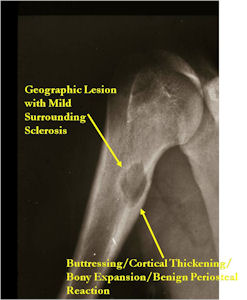

- Geographic, circumscribed lesion usually around 5cm in size.

- There may be expansion of bone, cortical thinning and cortical breakthrough. A soft tissue mass may accompany this lesion but the soft tissue component is usually contained by the periosteum.

- The periosteum remains intact around the soft tissue component. Might need a CT scan to detect the subtle calcification (Egg Shell Rim of Calcification) associated with an intact periosteal reaction

- The lesion may be entirely radiolucent but usually shows some degree of mineralization. Mineralization may appear stippled like cartilage but do not see chondroid pathologically. Mineralization is sometimes better detected on a CT scan rather than an x-ray.

- Usually less surrounding sclerosis than an osteoid osteoma.